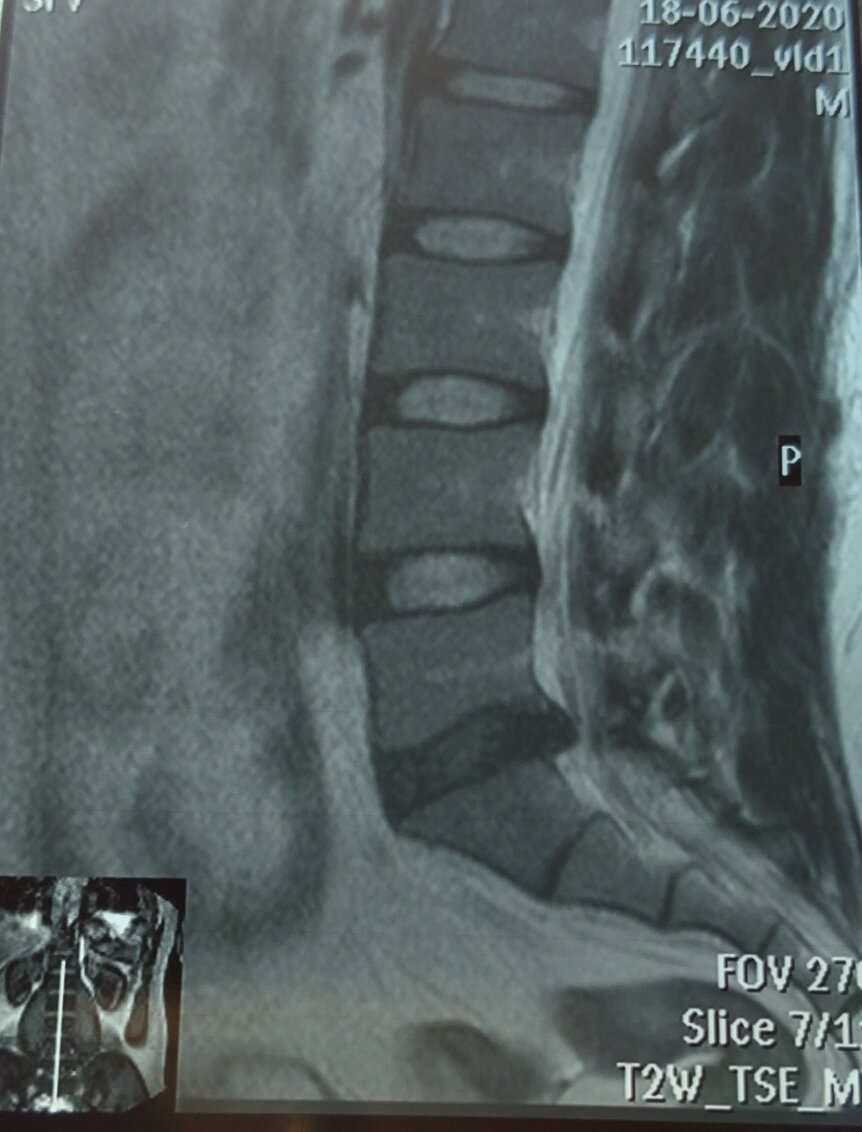

Недавно столкнулся с проблемой - защемление седалищного нерва. Тянущая боль. Отдает в правую ногу с частичным онемением. Причиной послужила грыжа L5/s1 диска. Делал МРТ.